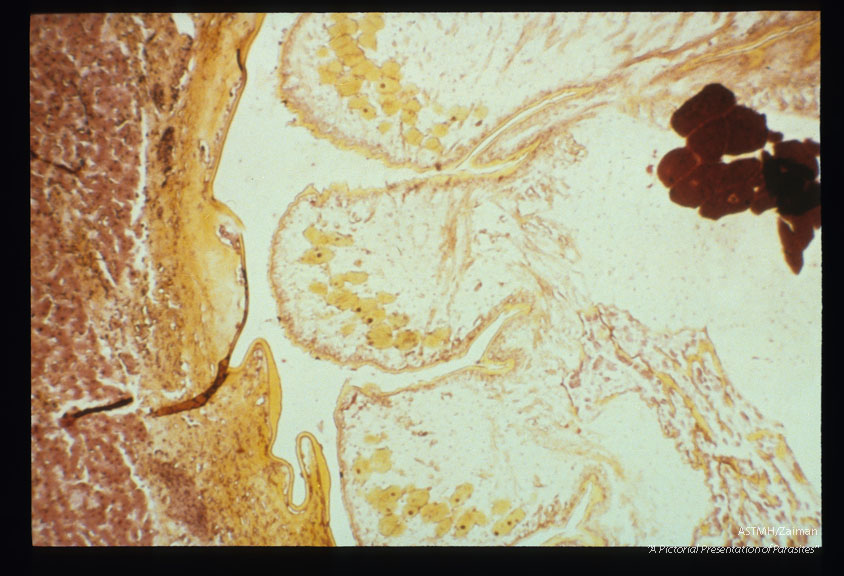

Liver sections at different magnifi­cations.

Armillifer armillatus

Description: Liver sections at different magnifi­cations.